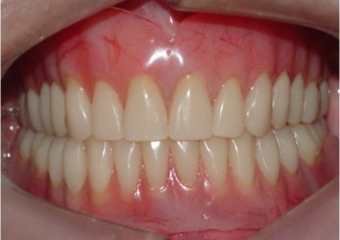

Prótese fixa inferior em resina instalada

Sorriso final, do caso terminado em janeiro de 2014